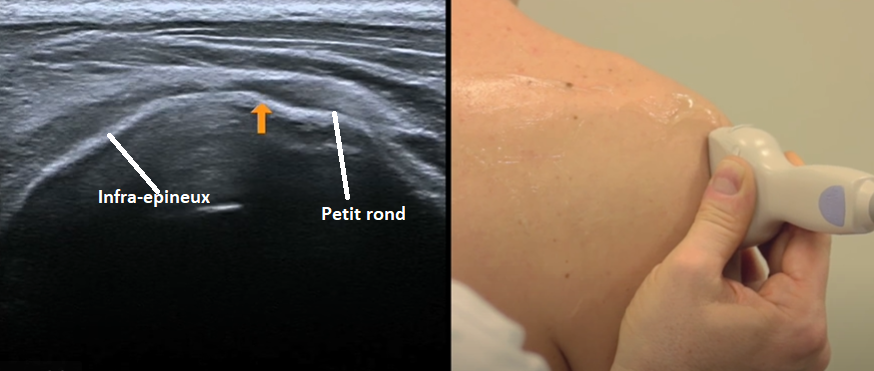

Infra-épineux

- Position neutre du début

- Coupe longitudinale

- Insertion sur le tubercule majeur (face oblique)

Coupe lnogitudinale

Petit rond

- Position neutre du début

- Sagittal sur le tubercule majeur

- Insertion du petit rond sur la face verticale

Coupe axiale